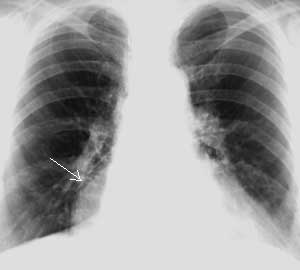

Рис. 3. Грыжа пищеводного отверстия диафрагмы. (Слева) На прямой ренгенограмме грудной клетки дополнительная тень в правом кардио-диафрагмальном угле. (Справа) На правой боковой ренгенограмме грудной клетки добавочная тень в заднем средостении.